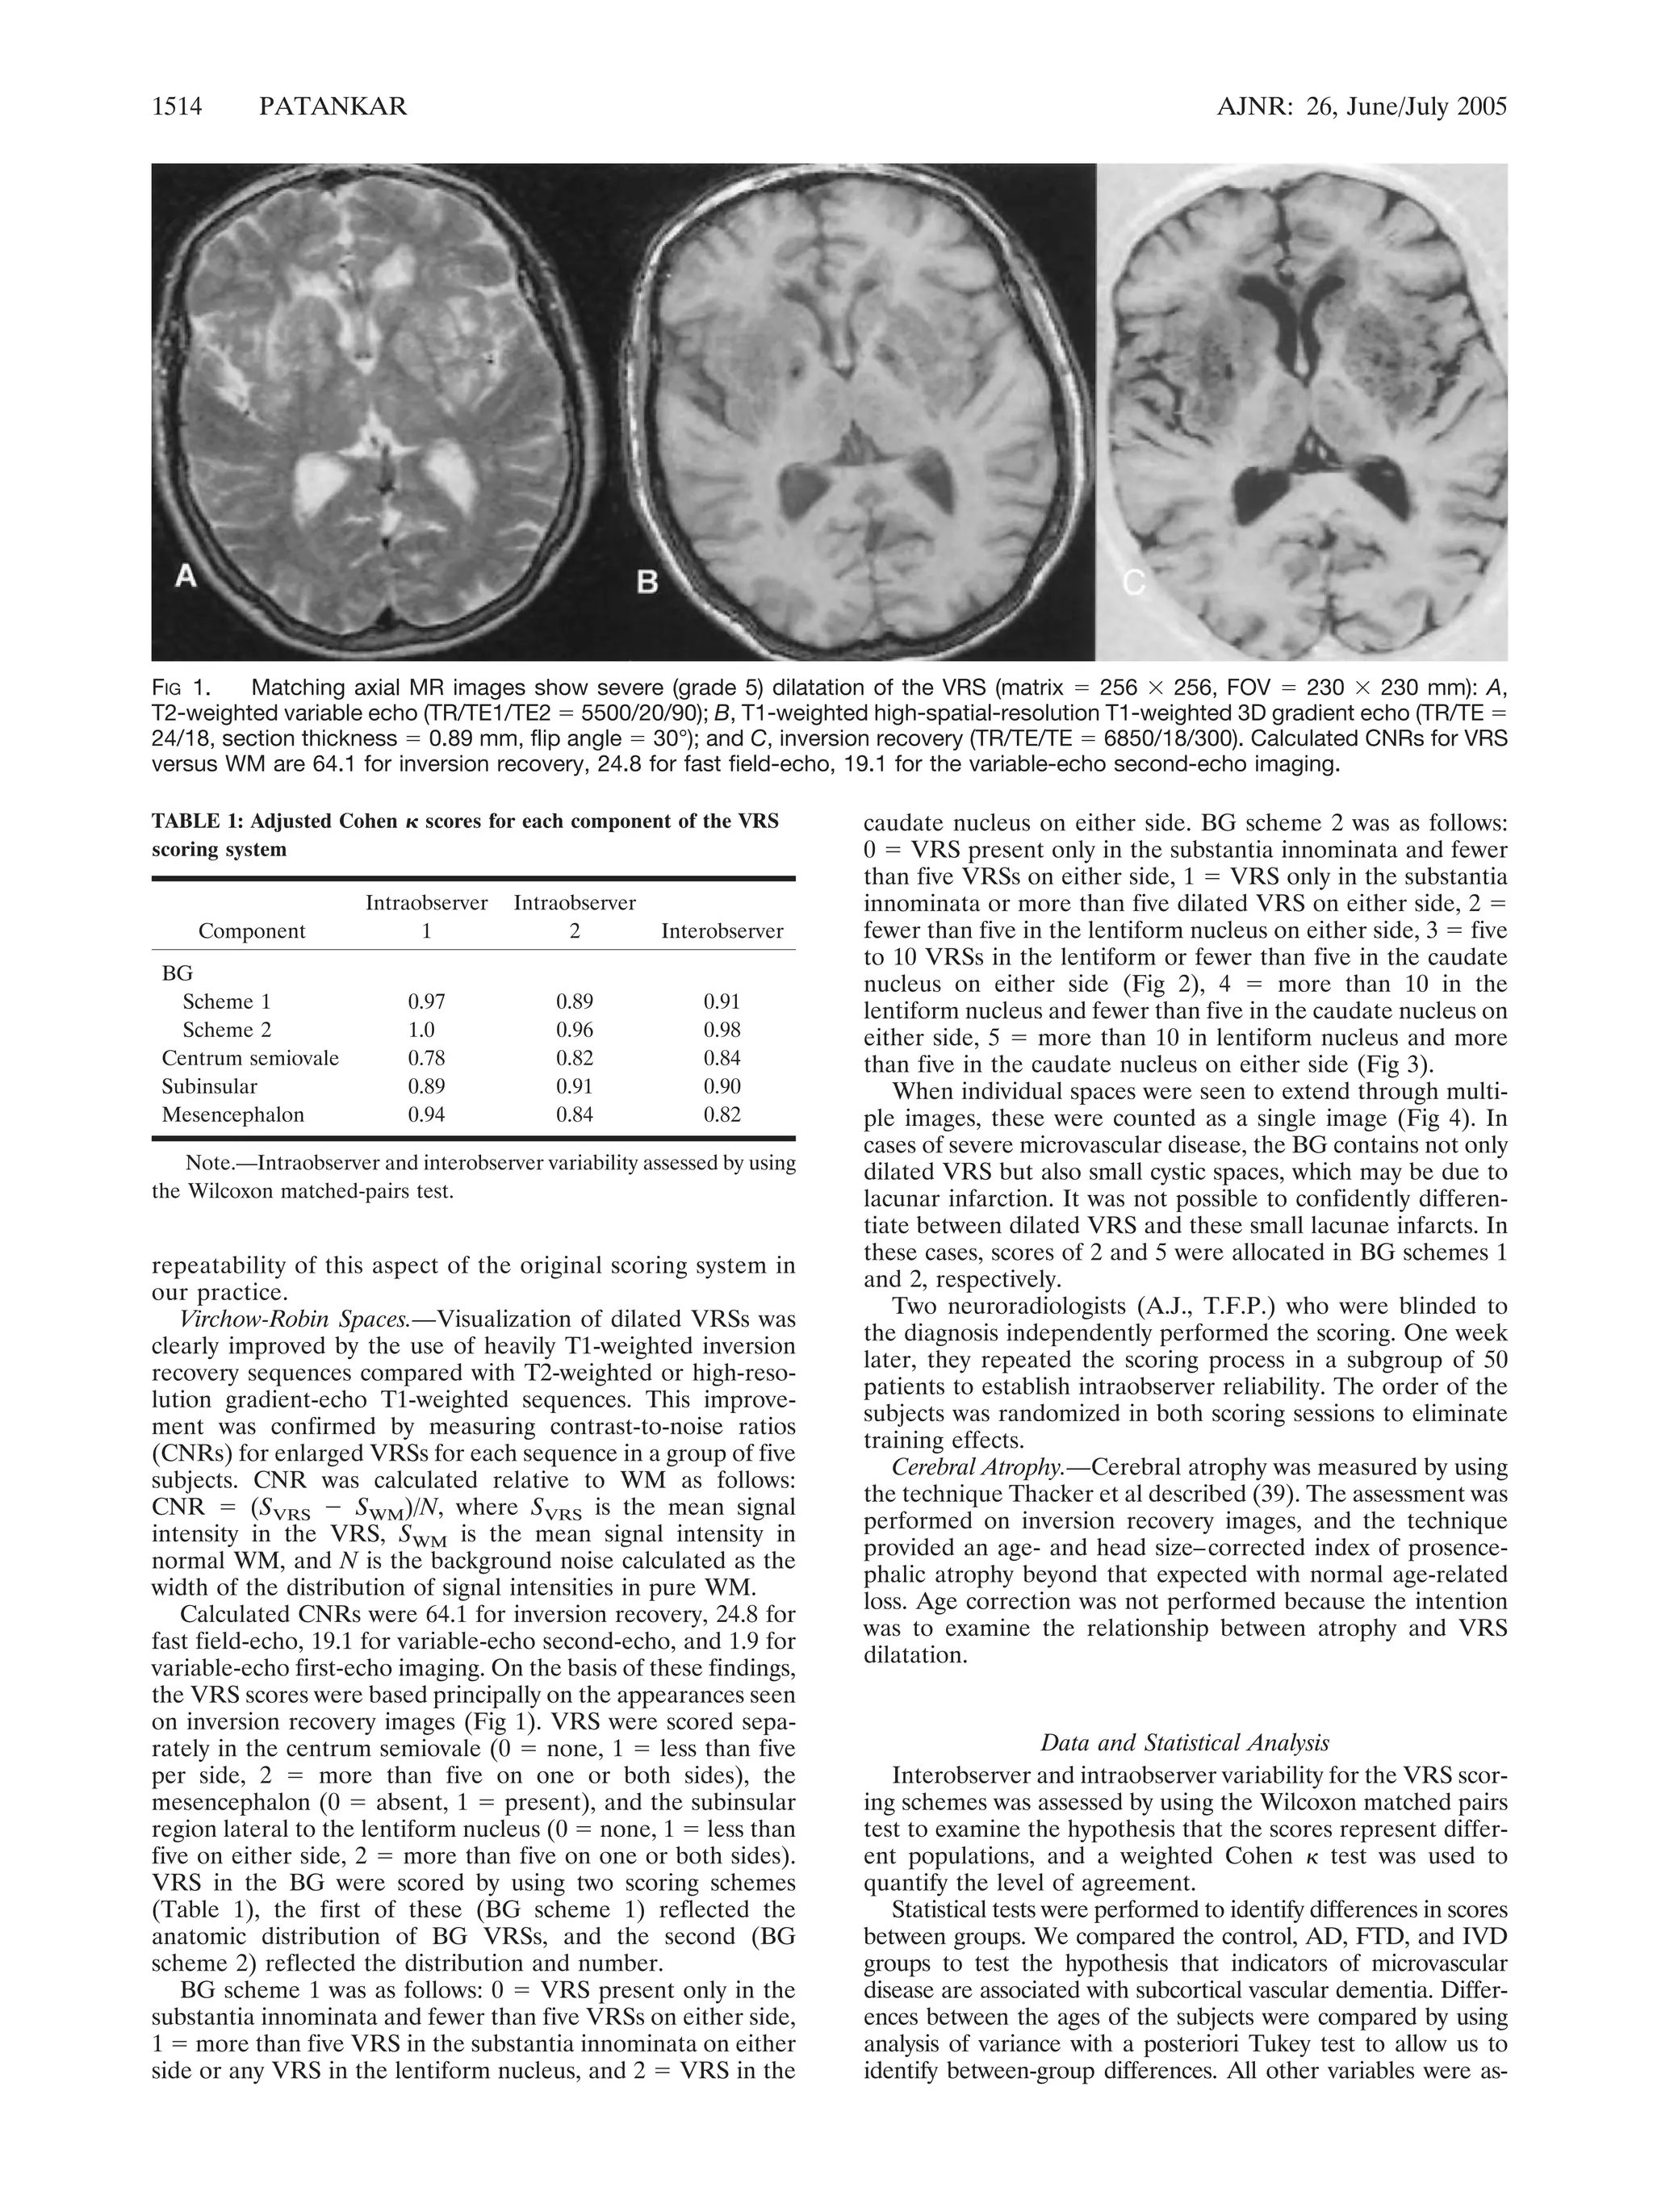

FIG 1. Matching axial MR images show severe (grade 5) dilatation of the VRS (matrix  256  256, FOV  230  230 mm): A,

T2-weighted variable echo (TR/TE1/TE2  5500/20/90); B, T1-weighted high-spatial-resolution T1-weighted 3D gradient echo (TR/TE

24/18, section thickness  0.89 mm, flip angle  30°); and C, inversion recovery (TR/TE/TE  6850/18/300). Calculated CNRs for VRS

versus WM are 64.1 for inversion recovery, 24.8 for fast field-echo, 19.1 for the variable-echo second-echo imaging.

Virchow-Robin Spaces.—Visualization of dilated VRSs was

clearly improved by the use of heavily T1-weighted inversion

recovery sequences compared with T2-weighted or high-reso-lution

gradient-echo T1-weighted sequences. This improve-ment

was confirmed by measuring contrast-to-noise ratios

(CNRs) for enlarged VRSs for each sequence in a group of five

subjects. CNR was calculated relative to WM as follows:

CNR  (SVRS  SWM)/N, where SVRS is the mean signal

intensity in the VRS, SWM is the mean signal intensity in

normal WM, and N is the background noise calculated as the

width of the distribution of signal intensities in pure WM.

Calculated CNRs were 64.1 for inversion recovery, 24.8 for

fast field-echo, 19.1 for variable-echo second-echo, and 1.9 for

variable-echo first-echo imaging. On the basis of these findings,

the VRS scores were based principally on the appearances seen

on inversion recovery images (Fig 1). VRS were scored sepa-rately